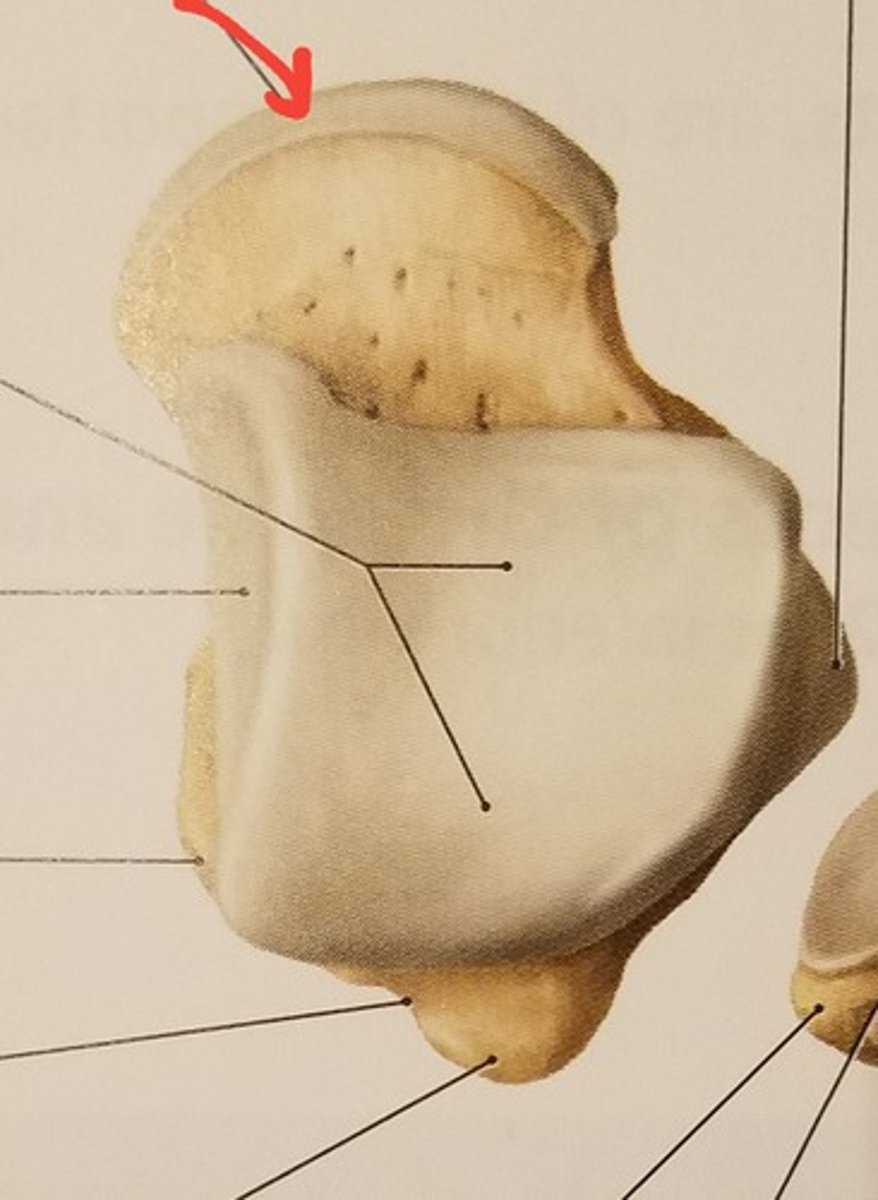

Patella

Apex

inferior surface for patellar ligament

Base

superior surface for quadriceps tendon

Medial articular surface (for medial condyle of femur; smaller)

Lateral articular surface (for lateral condyle of femur; bigger)